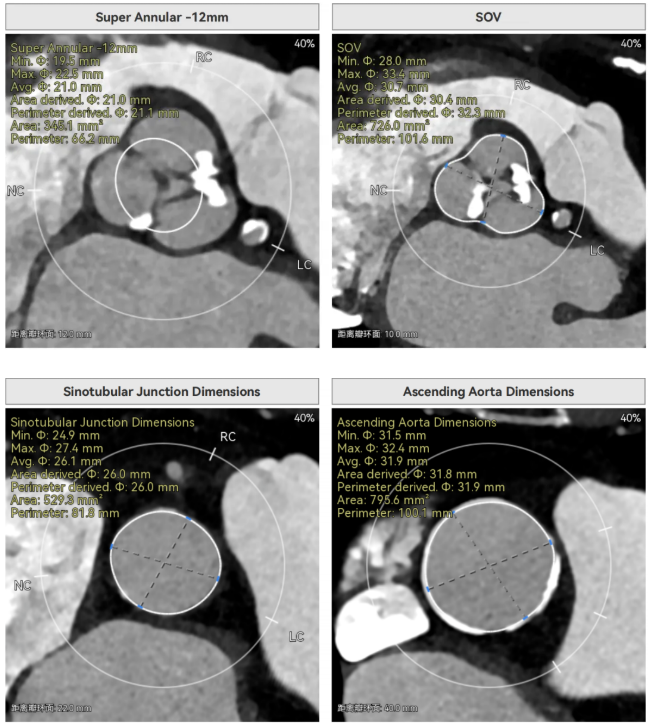

主动脉瓣环周长径21.9mm,小瓣环,LVOT直筒型结构;三叶瓣,左右融合(功能型二叶瓣),瓣叶轻微增厚并重度钙化,钙化主要分布在无冠窦瓣叶边缘及左右交界融合处,瓣上限制较重。

窦部空间适中,STJ内径偏小,升主动脉内径可。

双侧冠脉开口高度可,VTC空间充足,无冠脉风险,双冠内多处钙化,术中评估冠脉支架植入必要性。

左室内径较小,但合并轻度反流,低循环崩溃风险,室间隔膜部长度<3mm,有一定术后起搏器植入风险。